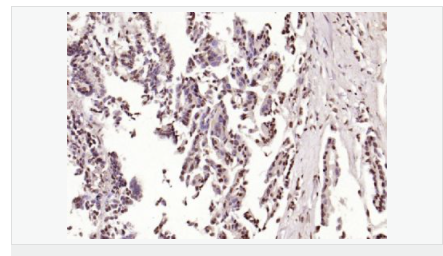

產品應用ELISA=1:5000-10000 IHC-P=1:100-500 IHC-F=1:100-500 Flow-Cyt=1μg/Test ICC=1:100 IF=1:100-500 (石蠟切片需做抗原修復)